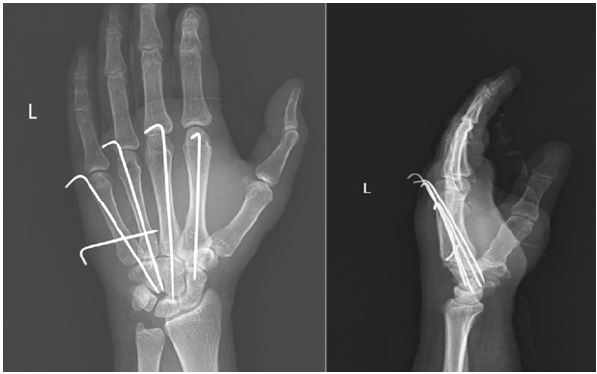

Closed reduction with manual traction and slab application was attempted, but it was unsuccessful as it was highly unstable. The patient was then taken up for surgery. Third CMC joint reduction to its articulation with the capitate was done and fixed with a retrograde K-wire. Once that was achieved, the 2nd, 4th, and 5th CMC joint reduction was done and fixed with K-wires. An additional intermetacarpal wire from 5th to 4th was inserted for extra stability for the highly mobile 4th and 5th CMC joints (Fig. 4).

Figure 4: Immediate post-operative radiographs after anatomical reduction of the carpometacarpal joints and K-wire fixation.

Dynamic fluoroscopy showed stable fixation and reduction. Postoperatively, a cock-up splint was applied, and immobilization was continued for 6 weeks. K-wires were removed after 6 weeks. Satisfactory reduction was maintained on re-examination after 6 weeks following cast removal (Fig. 5).